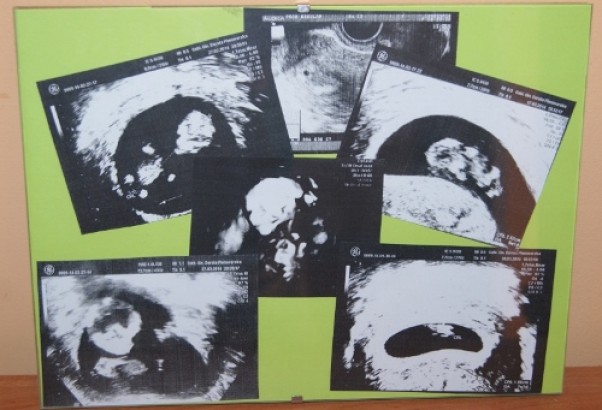

Kolaż z pierwszych zdjęć

Specjalnie dla tatusia zdjęcia naszego skarbka -od malutkiej kropki po dziewczynę aż 2,5kg!!!:)